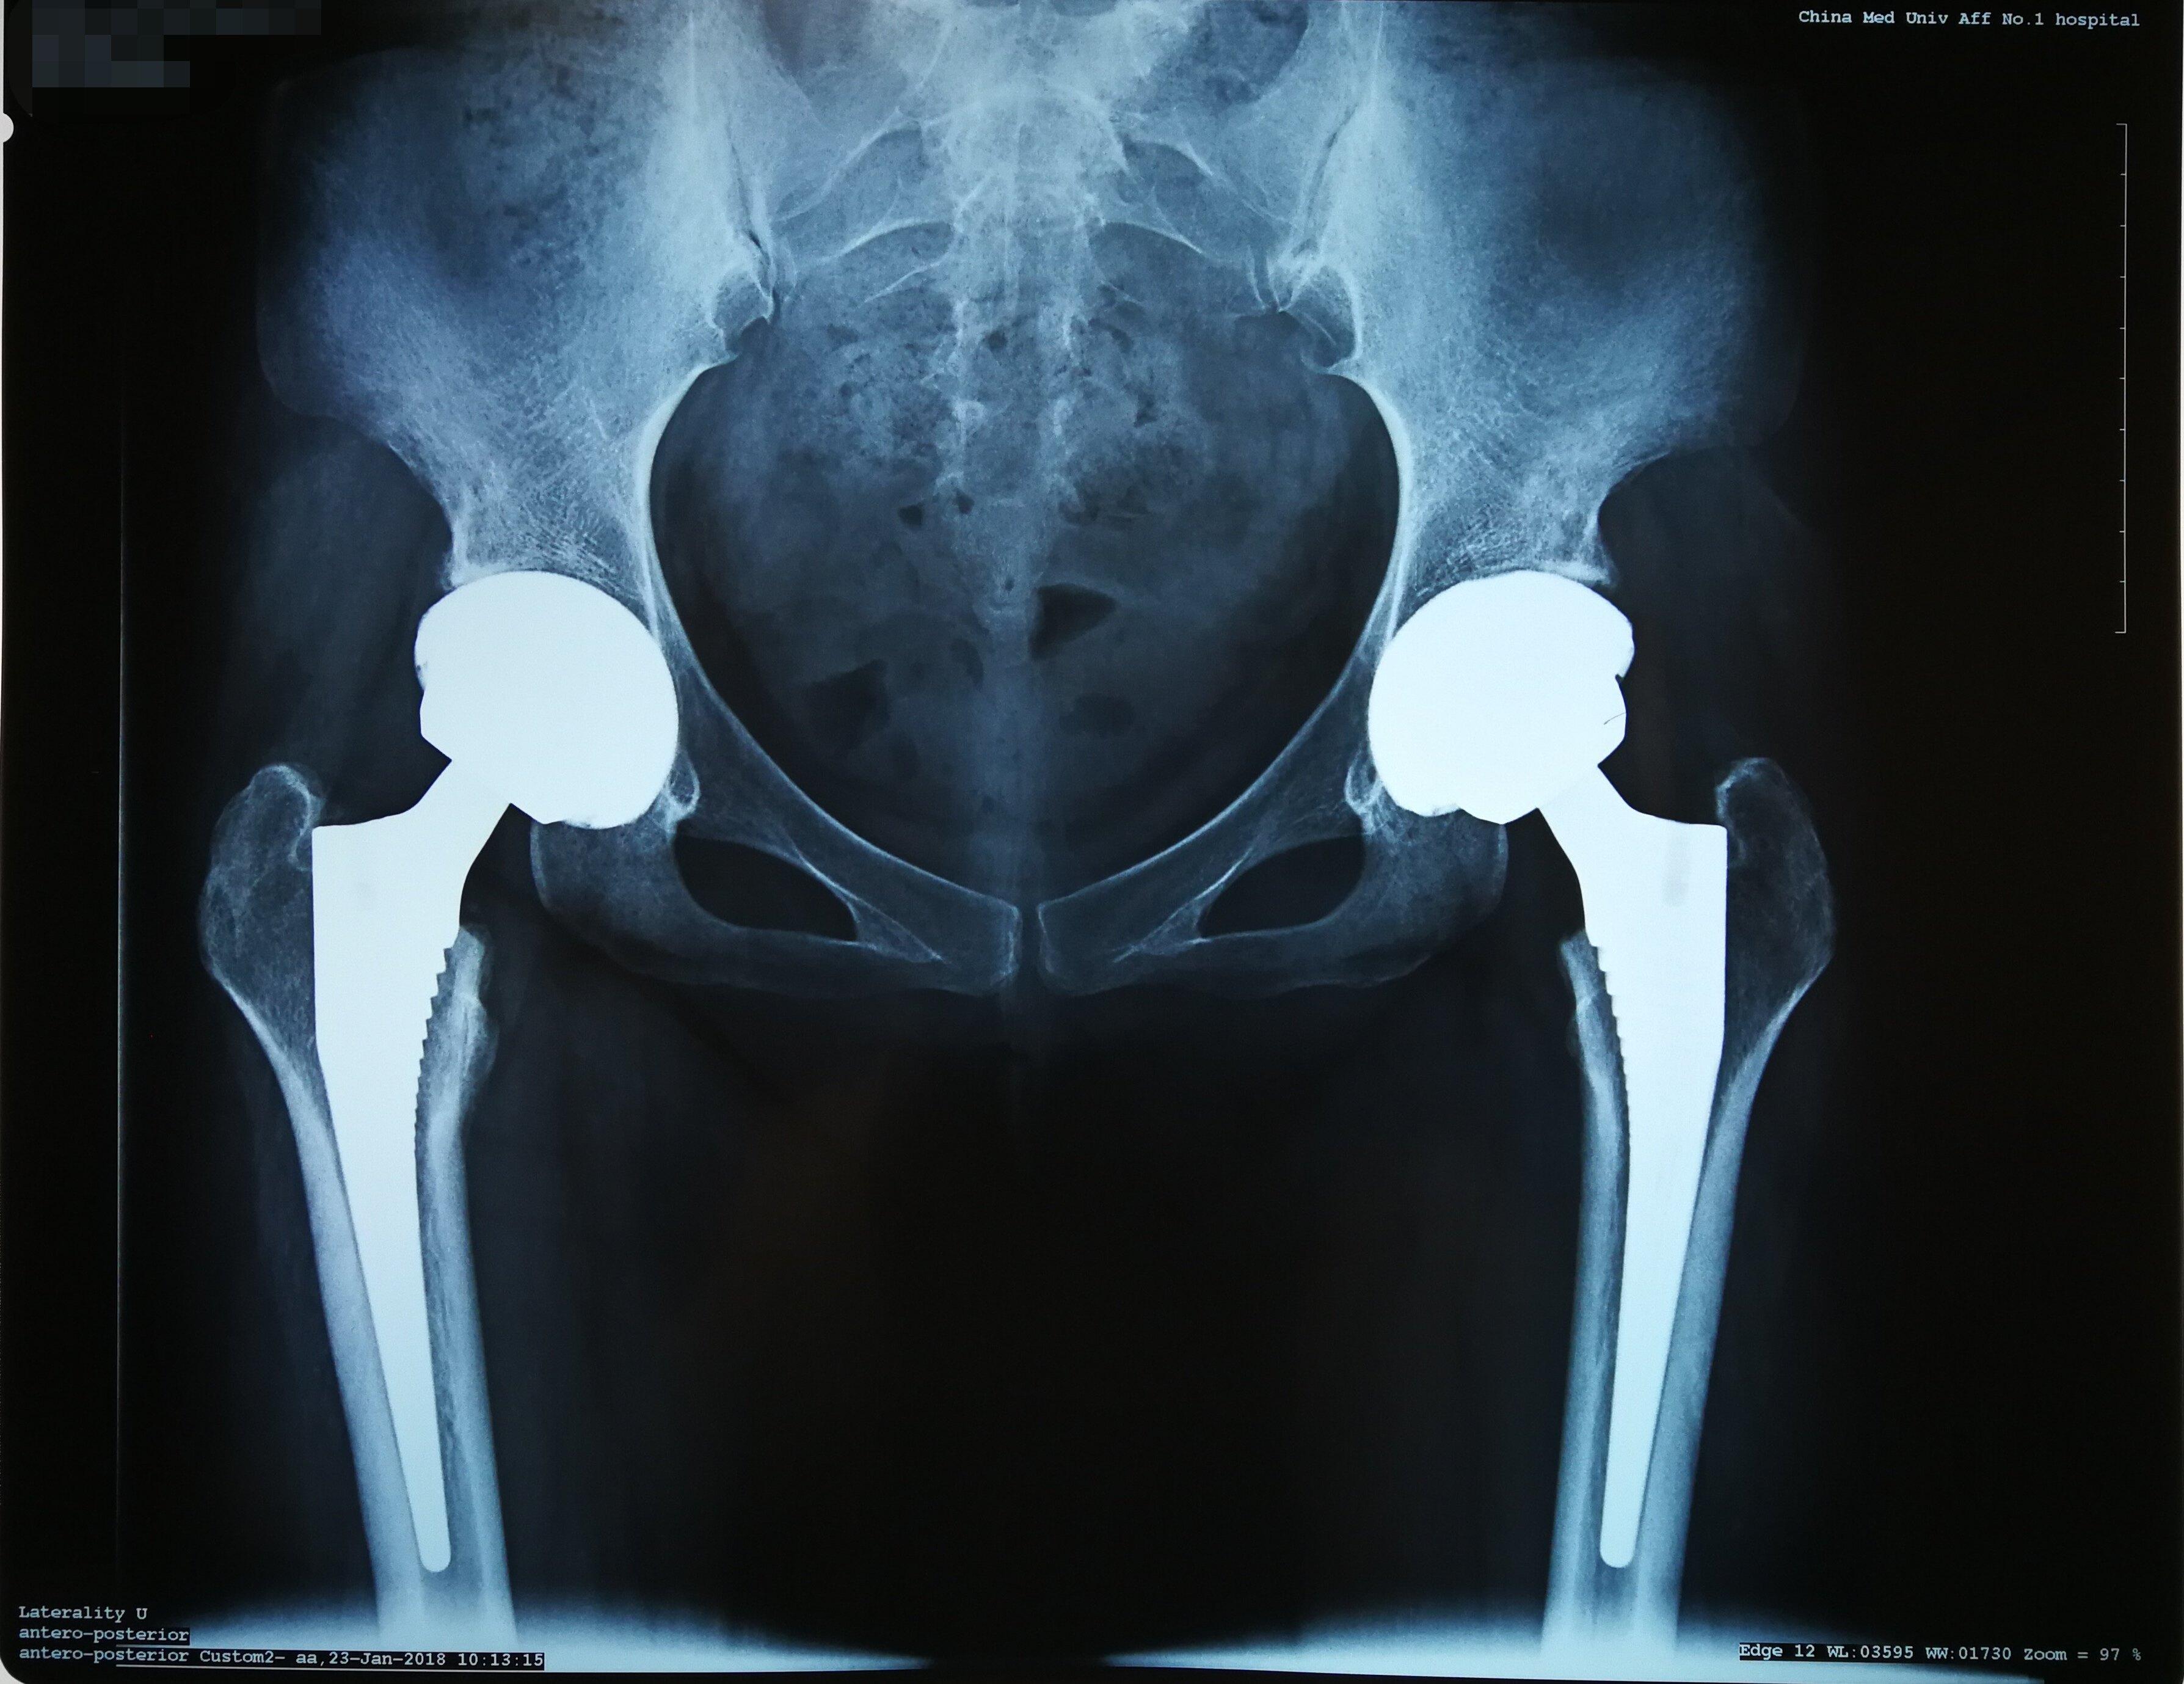

宣化区人民医院外二科首例同时双侧人工全髋关节置换术

双侧全髋关节置换术后假体无菌性松动翻修病例分享